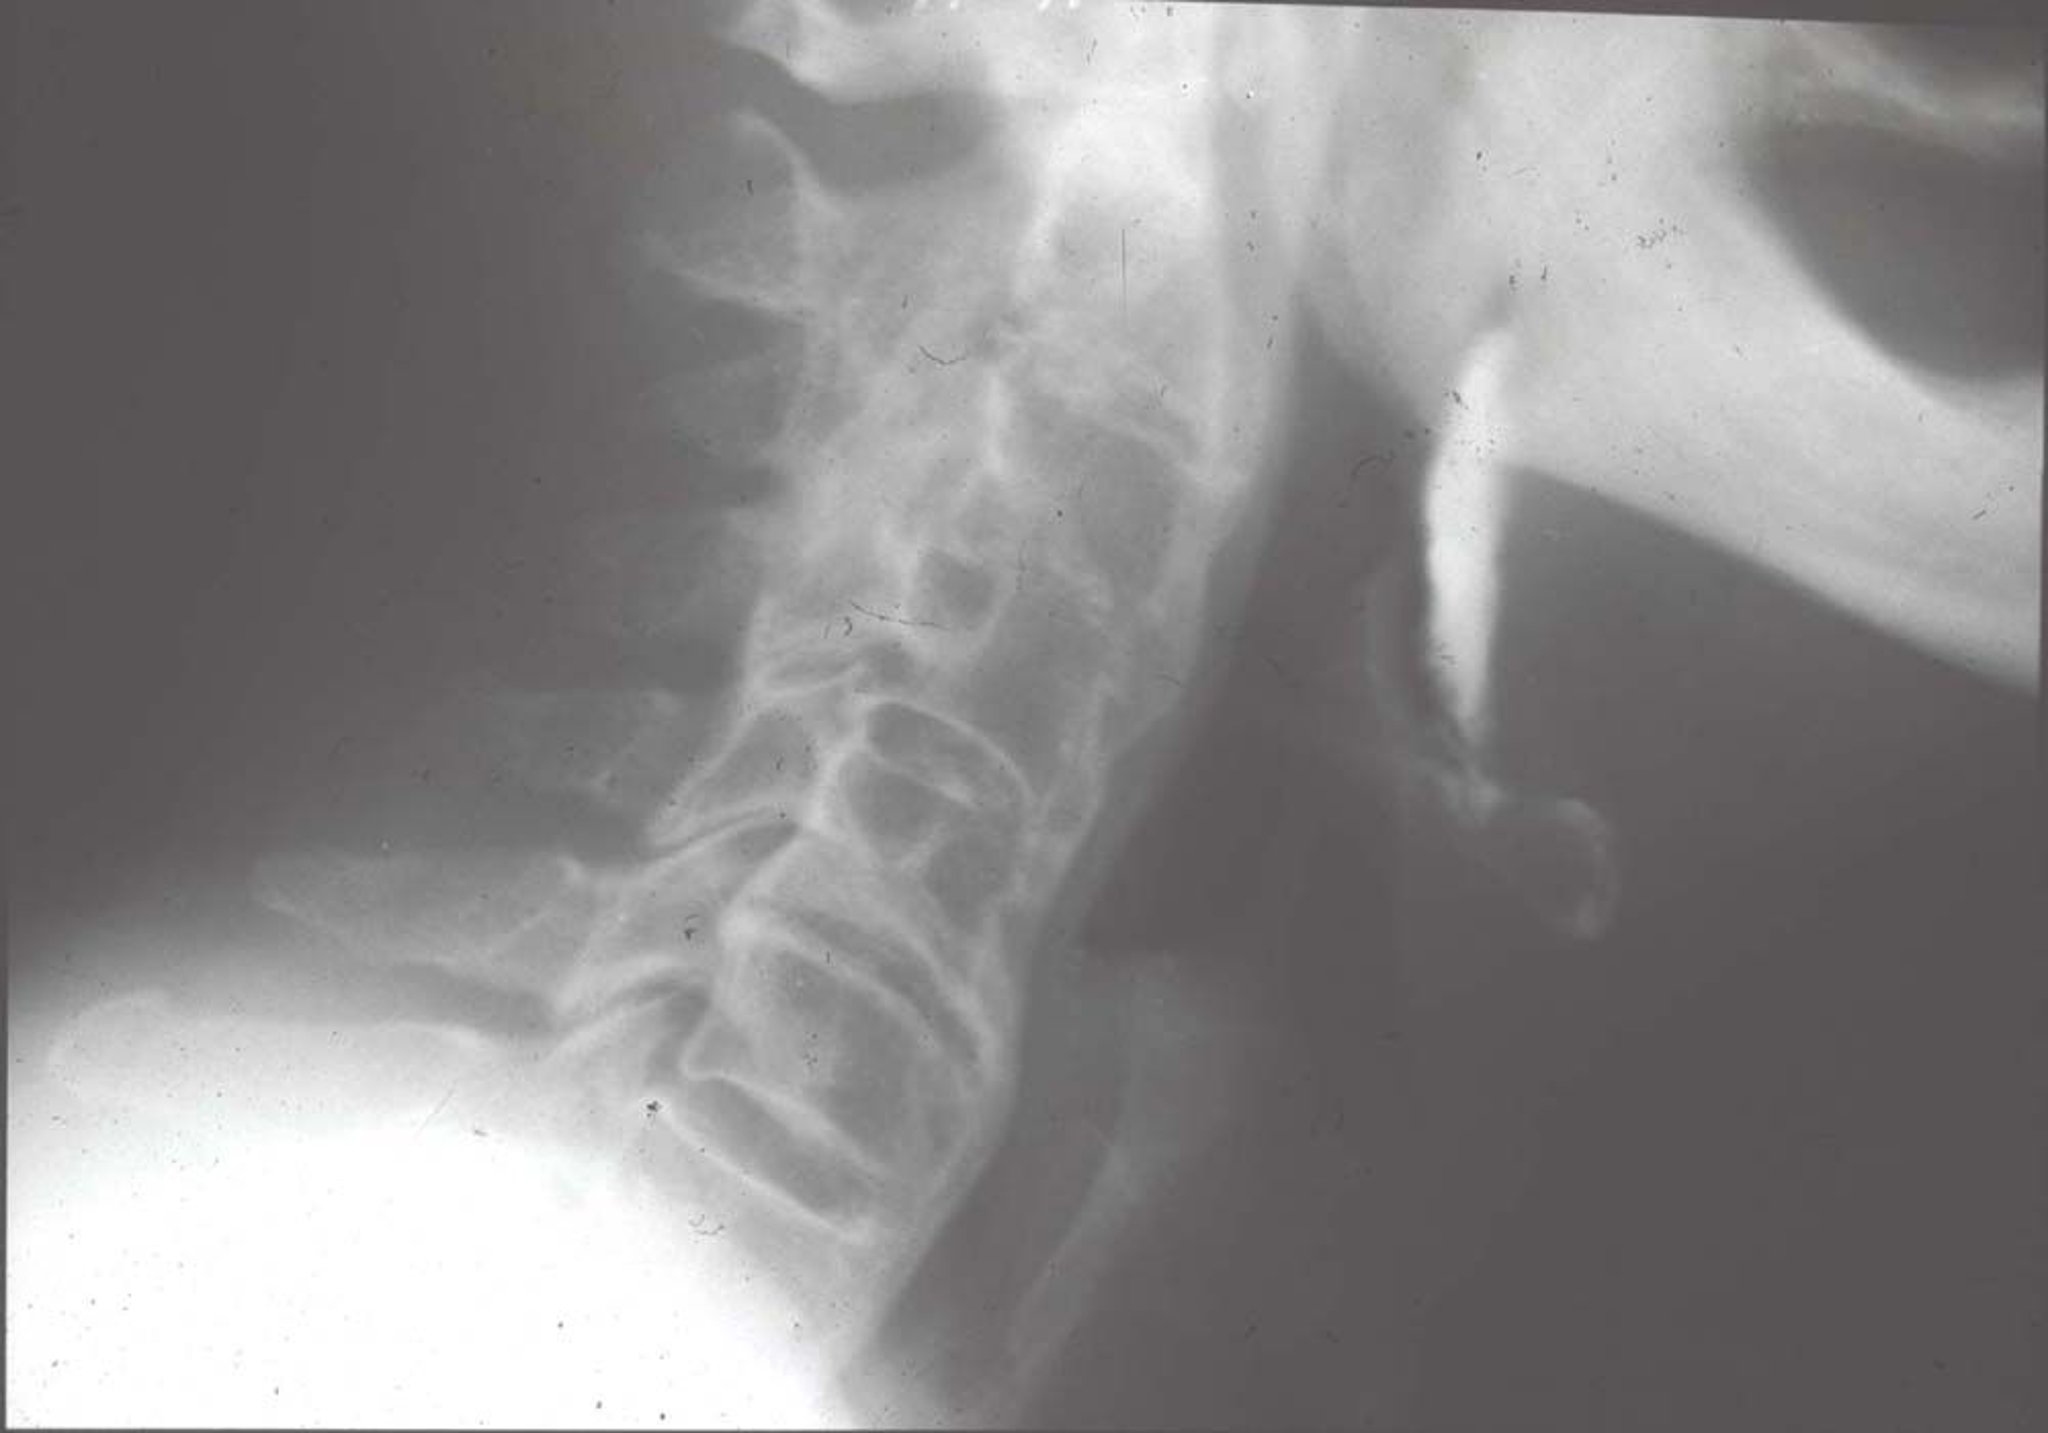

この頸椎側面像は,長期にわたる重度の強直性脊椎炎患者における硬直した頸椎を示している。靱帯骨棘形成,椎間関節の癒合,および脊椎周囲の靱帯石灰化によって脊椎が完全に強直している(「竹様脊柱」)。

By permission of the publisher.From Asim Khan M: Atlas of Rheumatology.Edited by G Hunder.Philadelphia, Current Medicine, 2005.